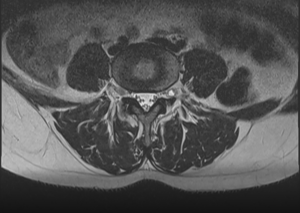

Болевой синдром в одном из поясничных отделов может присутствовать после проведения оперативного вмешательства на позвоночнике с целью уменьшения болевых ощущений, присутствующих в пояснице или нервных корешках. Иногда боли локализуются в нескольких зонах сразу и операция призвана их купировать. Тем не менее, после выхода пациента из наркоза, боли могут становиться еще интенсивнее и продолжительнее.

У пациентов, перенесших операцию на поясничном отделе позвоночного столба, боли могут возобновляться в 15-50% случаев. Процентное соотношение зависит от различных факторов, таких как тяжесть хирургического процесса, а также, способ оценки результатов проведенной процедуры.

Причины постоперационной боли

К сожалению, рецидив болей после операции на позвоночнике наступает все чаще с каждым новым хирургическим вмешательством. В позвоночном отделе, который подвергался операции, формируются спайки и рубцы, которые делают болевые ощущения еще интенсивнее. Выделяют следующие причины локализации болевых ощущений после оперативного процесса: